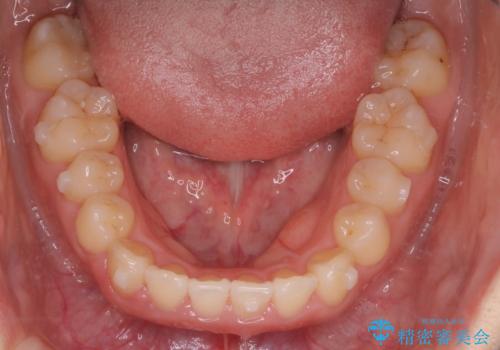

【インビザライン】前歯のがたつきを目立たない装置で治療

- 前歯の叢生を主訴に来院されました。目立たない装置を希望されたためインビザラインで治療を行いました。

IPRと拡大をし、叢生を治しました。右上2番は反対咬合でしたが短期間できれいに治りました。